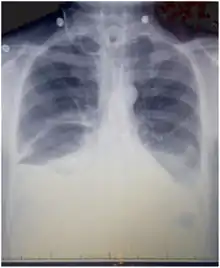

Chest X-rays can detect a chylothorax. It appears as a dense, homogenous area that obscures the costophrenic and cardiophrenic angles. Ultrasounds can also detect a chylothorax, which appears as an echoic region that is isodense with no septation or loculation. However, neither a normal chest x-ray nor an ultrasound can differentiate a chylothorax from any other type of pleural effusion.[1]

The symptoms of a chylothorax depend its size and the underlying cause. A small chylothorax may not cause any symptoms and only be detected on a chest X-ray performed for another reason. A large chylothorax may lead to breathlessness or a feeling of pressure in the chest, caused by fluid restricting the expansion of the lungs, although large chylothoraces may remain asymptomatic if the chylothorax has accumulated slowly, as the lungs may have had time to become used to the pressure. Fever or chest pain are not usually associated with chylothorax, as chyle does not generate inflammation by itself.[4]